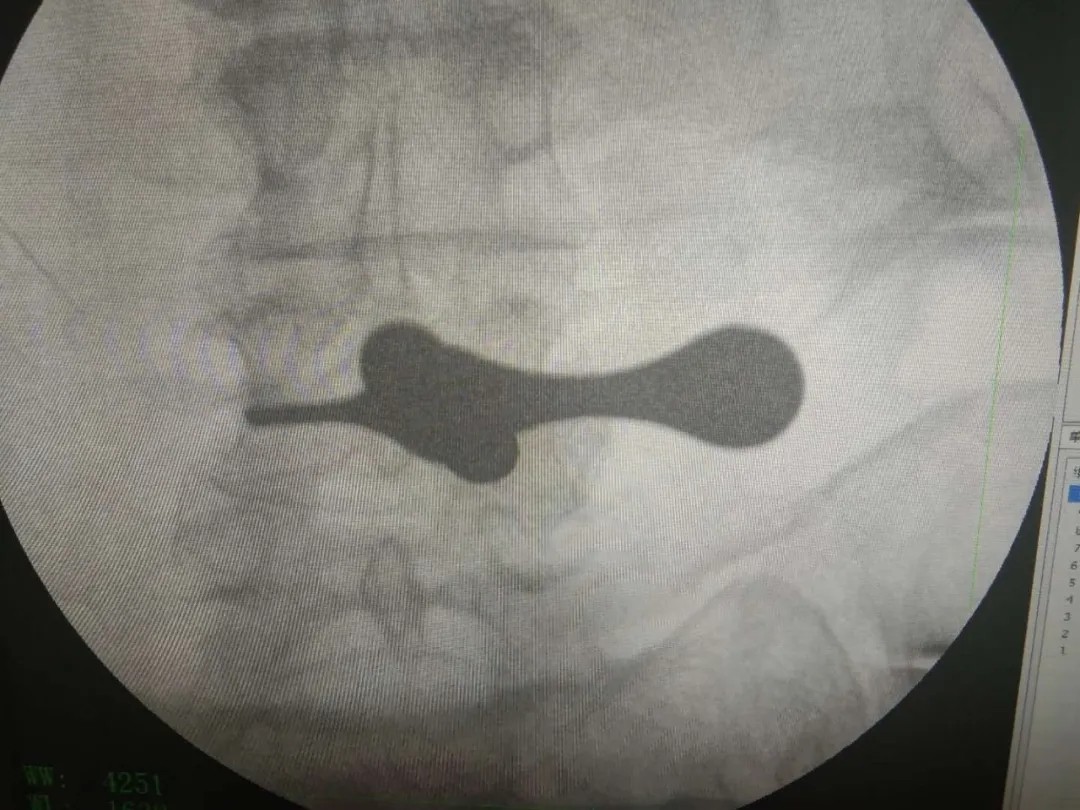

術后影像: